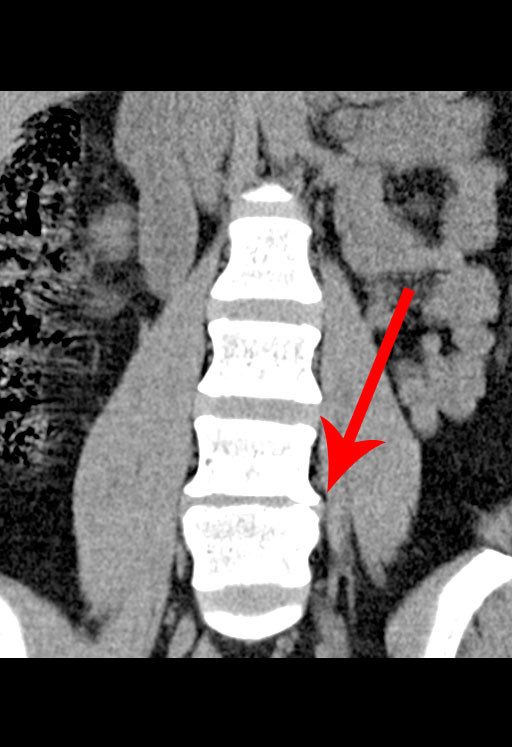

My name is Julie

Finley, and I recently ruptured my L4/L5 Lumbar disc so

bad, that I need to have surgery. It is pressing on my spinal cord,

causing extreme pain radiating down to my ankle, and

numbness/tingling/weakness in my left foot, causing a nerve disability called

"Foot Drop".

I also have bone degeneration around the disc. This has been an

issue amongst my doctors (and I need further testing) to determine

whether or not I will not just need a

discectomy, but

possibly a spinal fusion.

Here are some lovely images from my recent MRI and CT.